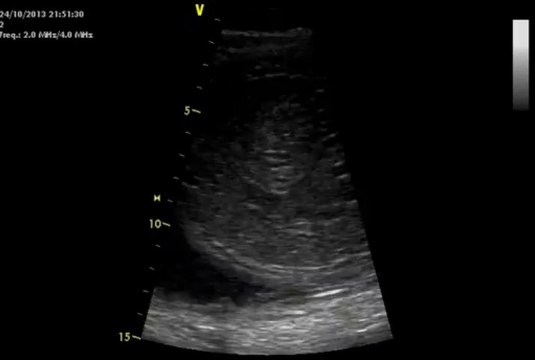

Echographie bebe 7 mois

Echographie bebe 5 mois grossesse Guide ; Evolution du fœtus à 7 mois bébé est sensible à la lumière A la fin du 7ème mois, le fœtus pèse environ un kilo et demi et mesure 40 cm Il écoute attentivement votre voix et celles de votre entourage Ses mouvements respiratoires ainsi que sa température interne se régulent, ses nerfs s'entourent d'une gaine (la myéline) Justement, l'échographie du 7e mois est une étape à ne pas rater afin que les conditions de la venue au monde de bébé soient des plus optimales Voici alors ce dont il faut savoir sur la dernière échographie de grossesse quand atelle lieu, à quoi elle sert

7e mois de grossesse 27e à 30e semaine (29 à 32 SA) le 15h25 Lecture en 3 min C'est l'heure de votre 3e écho !J'aime 22 mai 08 à 17h12 Je l'ai passé vendredi dernier à 34sa3 (32sg3) et elle avait un poids estimé de 2308kg, toujours avec la marge d'erreurLa troisième et dernière échographie de grossesse a lieu aux alentours de 32 SA (fin du 7ème mois, début du 8ème) Elle n'est pas obligatoire mais fait partie des examens systématiquement

Votre bébé lors du 7ème mois de grossesse Au terme du 7ème mois, votre bébé va mesurer une quarantaine de centimètres et peser plus d'un kilo et demi il va donc commencer à se sentir à l'étroit, et limiter ses mouvements Il est désormais très attentif à vos conversations et à la musique que vous lui passez Ses ongles commencent à se former, des cheveux très fins L'échographie du premier trimestre a lieu entre 11 semaines et 13,5 semaines d'aménorrhée "Dans notre cabinet, nous préférons la faire entre la 12ème semaine et la 13ème semaine d'aménorrhée (13 SA), soit entre la 10e et la 11e semaine de grossesse, afin d'avoir une meilleure visualisation, notamment pour la mesure de la clartéComme votre bidon, votre bébé continue de grossir et, pour la première fois, vous sentez que la fin est proche, même s'il vous reste encore deux mois On fait le point sur ce 7e mois de grossesse